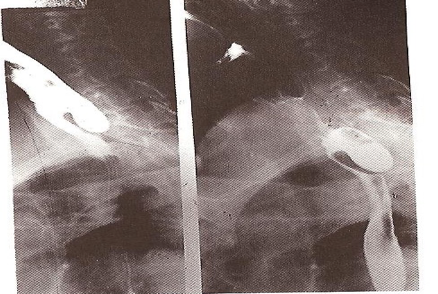

- Killian’s Dehiscence: Potential gap between thyropharyngeus and cricopharyngeus

zenkers diverticulum, barium swallow, laryngeal pouch, management; …